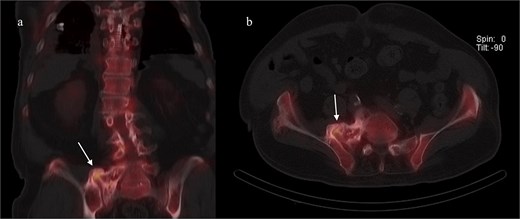

A CT of the pelvis showed significant hyperostosis along the anterior right SI joint and a pseudoarthrosis between the L5 transverse process and the sacral ala that was osteoblastic-appearing in nature (Fig. 1). A SPECT-CT demonstrated increased uptake along the same area, suggestive of inflammatory degenerative changes (Fig. 2).

Coronal (left) and axial (right) views of pelvic CT-SPECT highlighted increased uptake along the right SI joint, suggestive of inflammation (arrows).